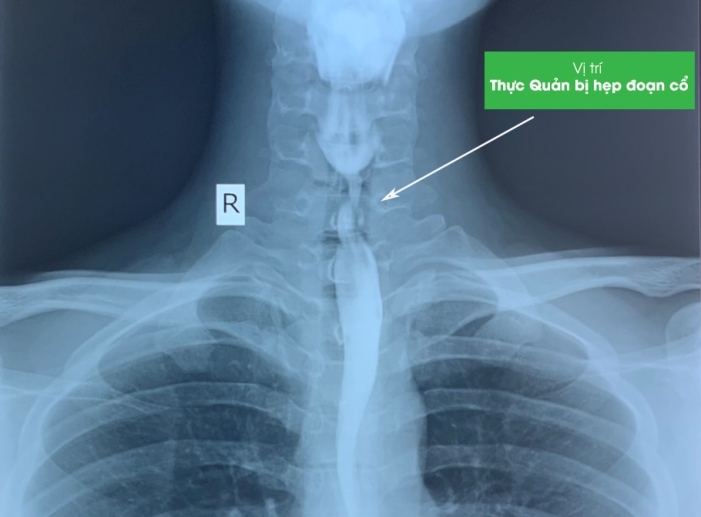

Trước đó, ngày 24/8, anh T.V.N (SN 1999, Đà Nẵng) đến bệnh viện thăm khám trong tình trạng nuốt khó, nuốt nghẹn, đặc biệt là các thức ăn cứng. Qua kết quả nội soi cho thấy, anh N. bị hẹp khít thực quản đoạn cổ, kéo dài một đoạn khoảng 20 mm.

Thực quản nam bệnh nhân bị bỏng làm hẹp, cản trở lưu thông

Theo các bác sĩ, chính hóa chất này đã gây bỏng thực quản và qua thời gian đã hình thành sẹo làm hẹp dần lòng thực quản, cản trở lưu thông, vận chuyển thức ăn dẫn đến khó nuốt. Nếu càng để lâu, tình trạng khó nuốt sẽ tăng dần và có thể không nuốt được cả chất lỏng.